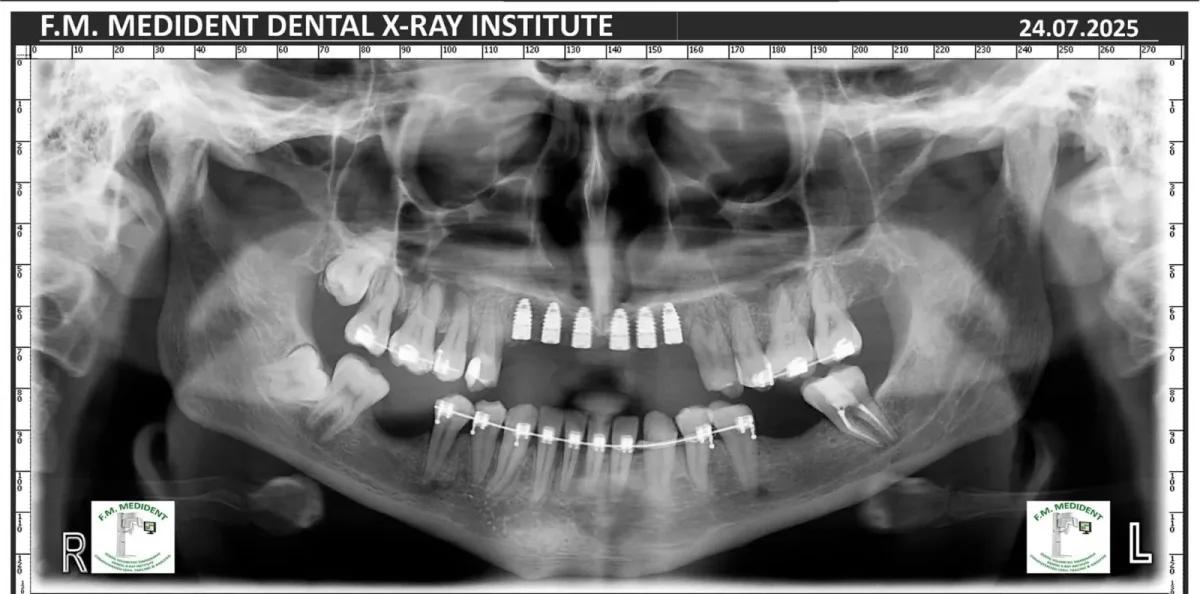

Cazuri reale înainte și după, din tratamente realizate în clinică.

Înainte

După